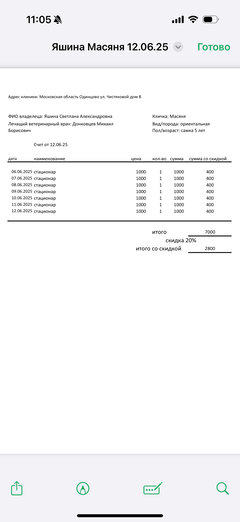

Ярко выраженная болезненность в области крестца, на обезболе полегче. По результатам приема невролога проведена миелография - множественная компрессия, возможно опухоль, возможно грыжа, нужно удалять...

Баланс на 12.06.2025: минус 32 396,34